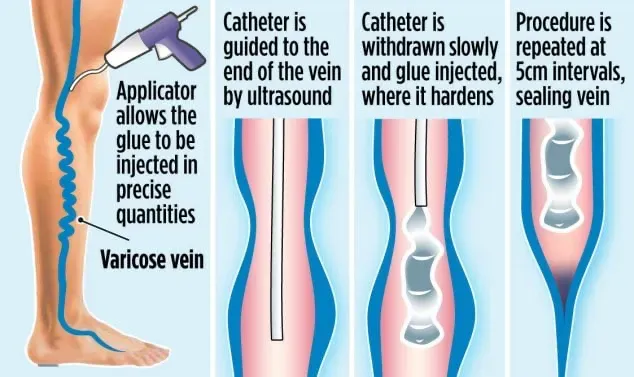

目前广泛应用的非热导管消融技术主要有机械化学消融装置(mechanochemical ablation devices, MOCA)和氰基丙烯酸酯胶(cyanoacrylate glue, CAG)。在一些国家,对于大多数专门的静脉诊所,患者的治疗都是在门诊进行的,只使用局部或肿胀麻醉,不使用任何镇静、区域阻滞或全身麻醉。这种方法使患者可以步行,接受治疗,然后完全恢复活动回家,并将DVT等并发症的风险降至最低。这是因为病人在术前不需要禁食。

TIPS: Cyanoacrylate腔内消融:氰基丙烯酸酯消融术是一种由医生执行的手术,目的是用医用粘合剂通过小导管输送来关闭病变静脉腔。这是一个30到60分钟的门诊手术(同一天),可以在双腿上进行,疼痛最小,不需要肿胀麻醉。

非热腔内技术的另一个优点是避免对附近皮肤或神经的任何热损伤,这特别适用于膝下大隐静脉 (GSV) 和远端小隐静脉 (SSV),这两个部位分别与隐神经和腓肠神经密切相关。

在这种环境下,EVTA手术中最痛苦的部分已被证明是肿胀麻醉126因此,只要与EVTA同样有效,任何不需要肿胀麻醉的手术对患者都有好处。